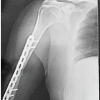

A differential diagnosis of aneurysmal bone cyst or giant cell tumour with pathological fracture was made. Under spinal anaesthesia and strict aseptic precautions, the lesion was curetted and the cavity was filled with iliac bone grafts (Fig 3, 4).

The curetted specimen was sent again for histopathological examination and the diagnosis was confirmed (Fig 5). The wound was closed, dressed and below knee posterior plaster slab was applied.